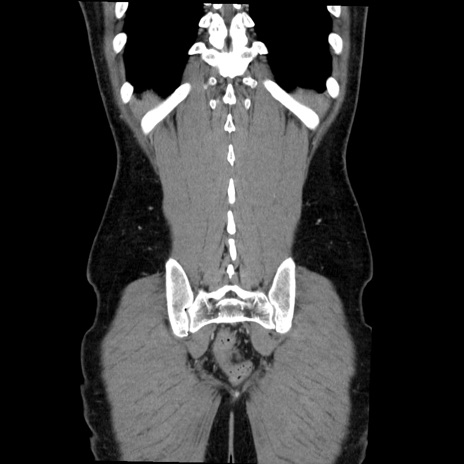

症例36(冠状断像)

【症例】20歳代 男性

【主訴】心窩部痛

【現病歴】今朝より上腹部痛あり。一旦軽快していたが再度出現したため救急要請。昨日夕に白身の魚を含む刺身を食べた。

【身体所見】BP 136/89mmHg、HR 74/min、BT 37.0℃、腹部:膨満、軟、心窩部に圧痛あり。反跳痛なし、筋性防御なし、腸雑音やや亢進あり。

【データ】WBC 17700、CRP 0.48